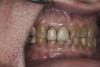

(9.) Preoperative right lateral, closed view.

Figure 9

(10.) Preoperative anterior, closed view. Note the end-to-end occlusion of the anterior teeth and the wear on the incisors and centrals resulting in no anterior or canine guidance.

Figure 10

(11.) Preoperative left lateral, closed view.

Figure 11